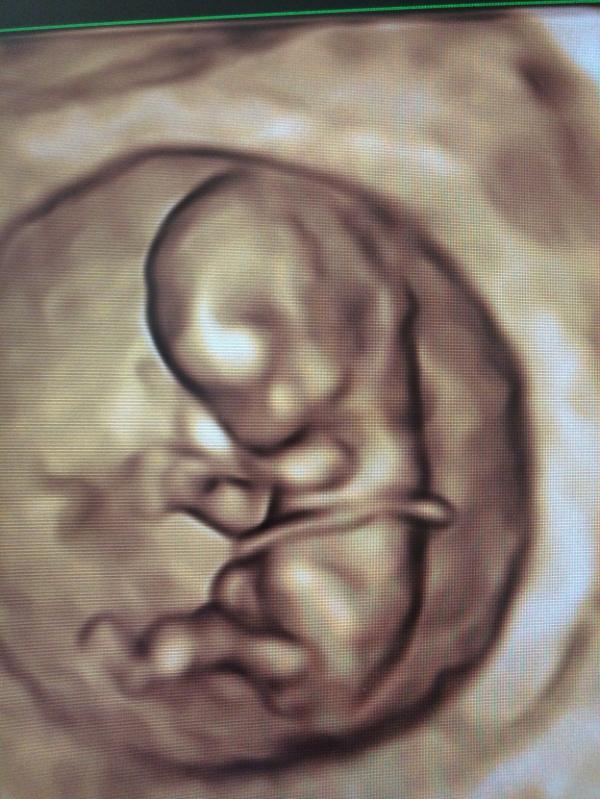

Я сходила на I скрининг к Отарян Каринэ, как и собиралась.

Стоимость - УЗИ(4000руб.), биохимия крови(1500руб.)

Ощущения - это превосходный врач!

Чуткий, заботливый, разговорчивый. Видно, что свою работу любит, людей любит.

Радуется и восхищается вместе с клиентом. Все подробно рассказывает и показывает, попутно успокаивая, если что-то кажется клиенту волнительным.

Очень деликатно узнает, хотят ли клиенты знать пол. Не огорошивает информацией.

Отчаянно рекомендую её.

На второй скрининг пойду опять к ней 100%!!!